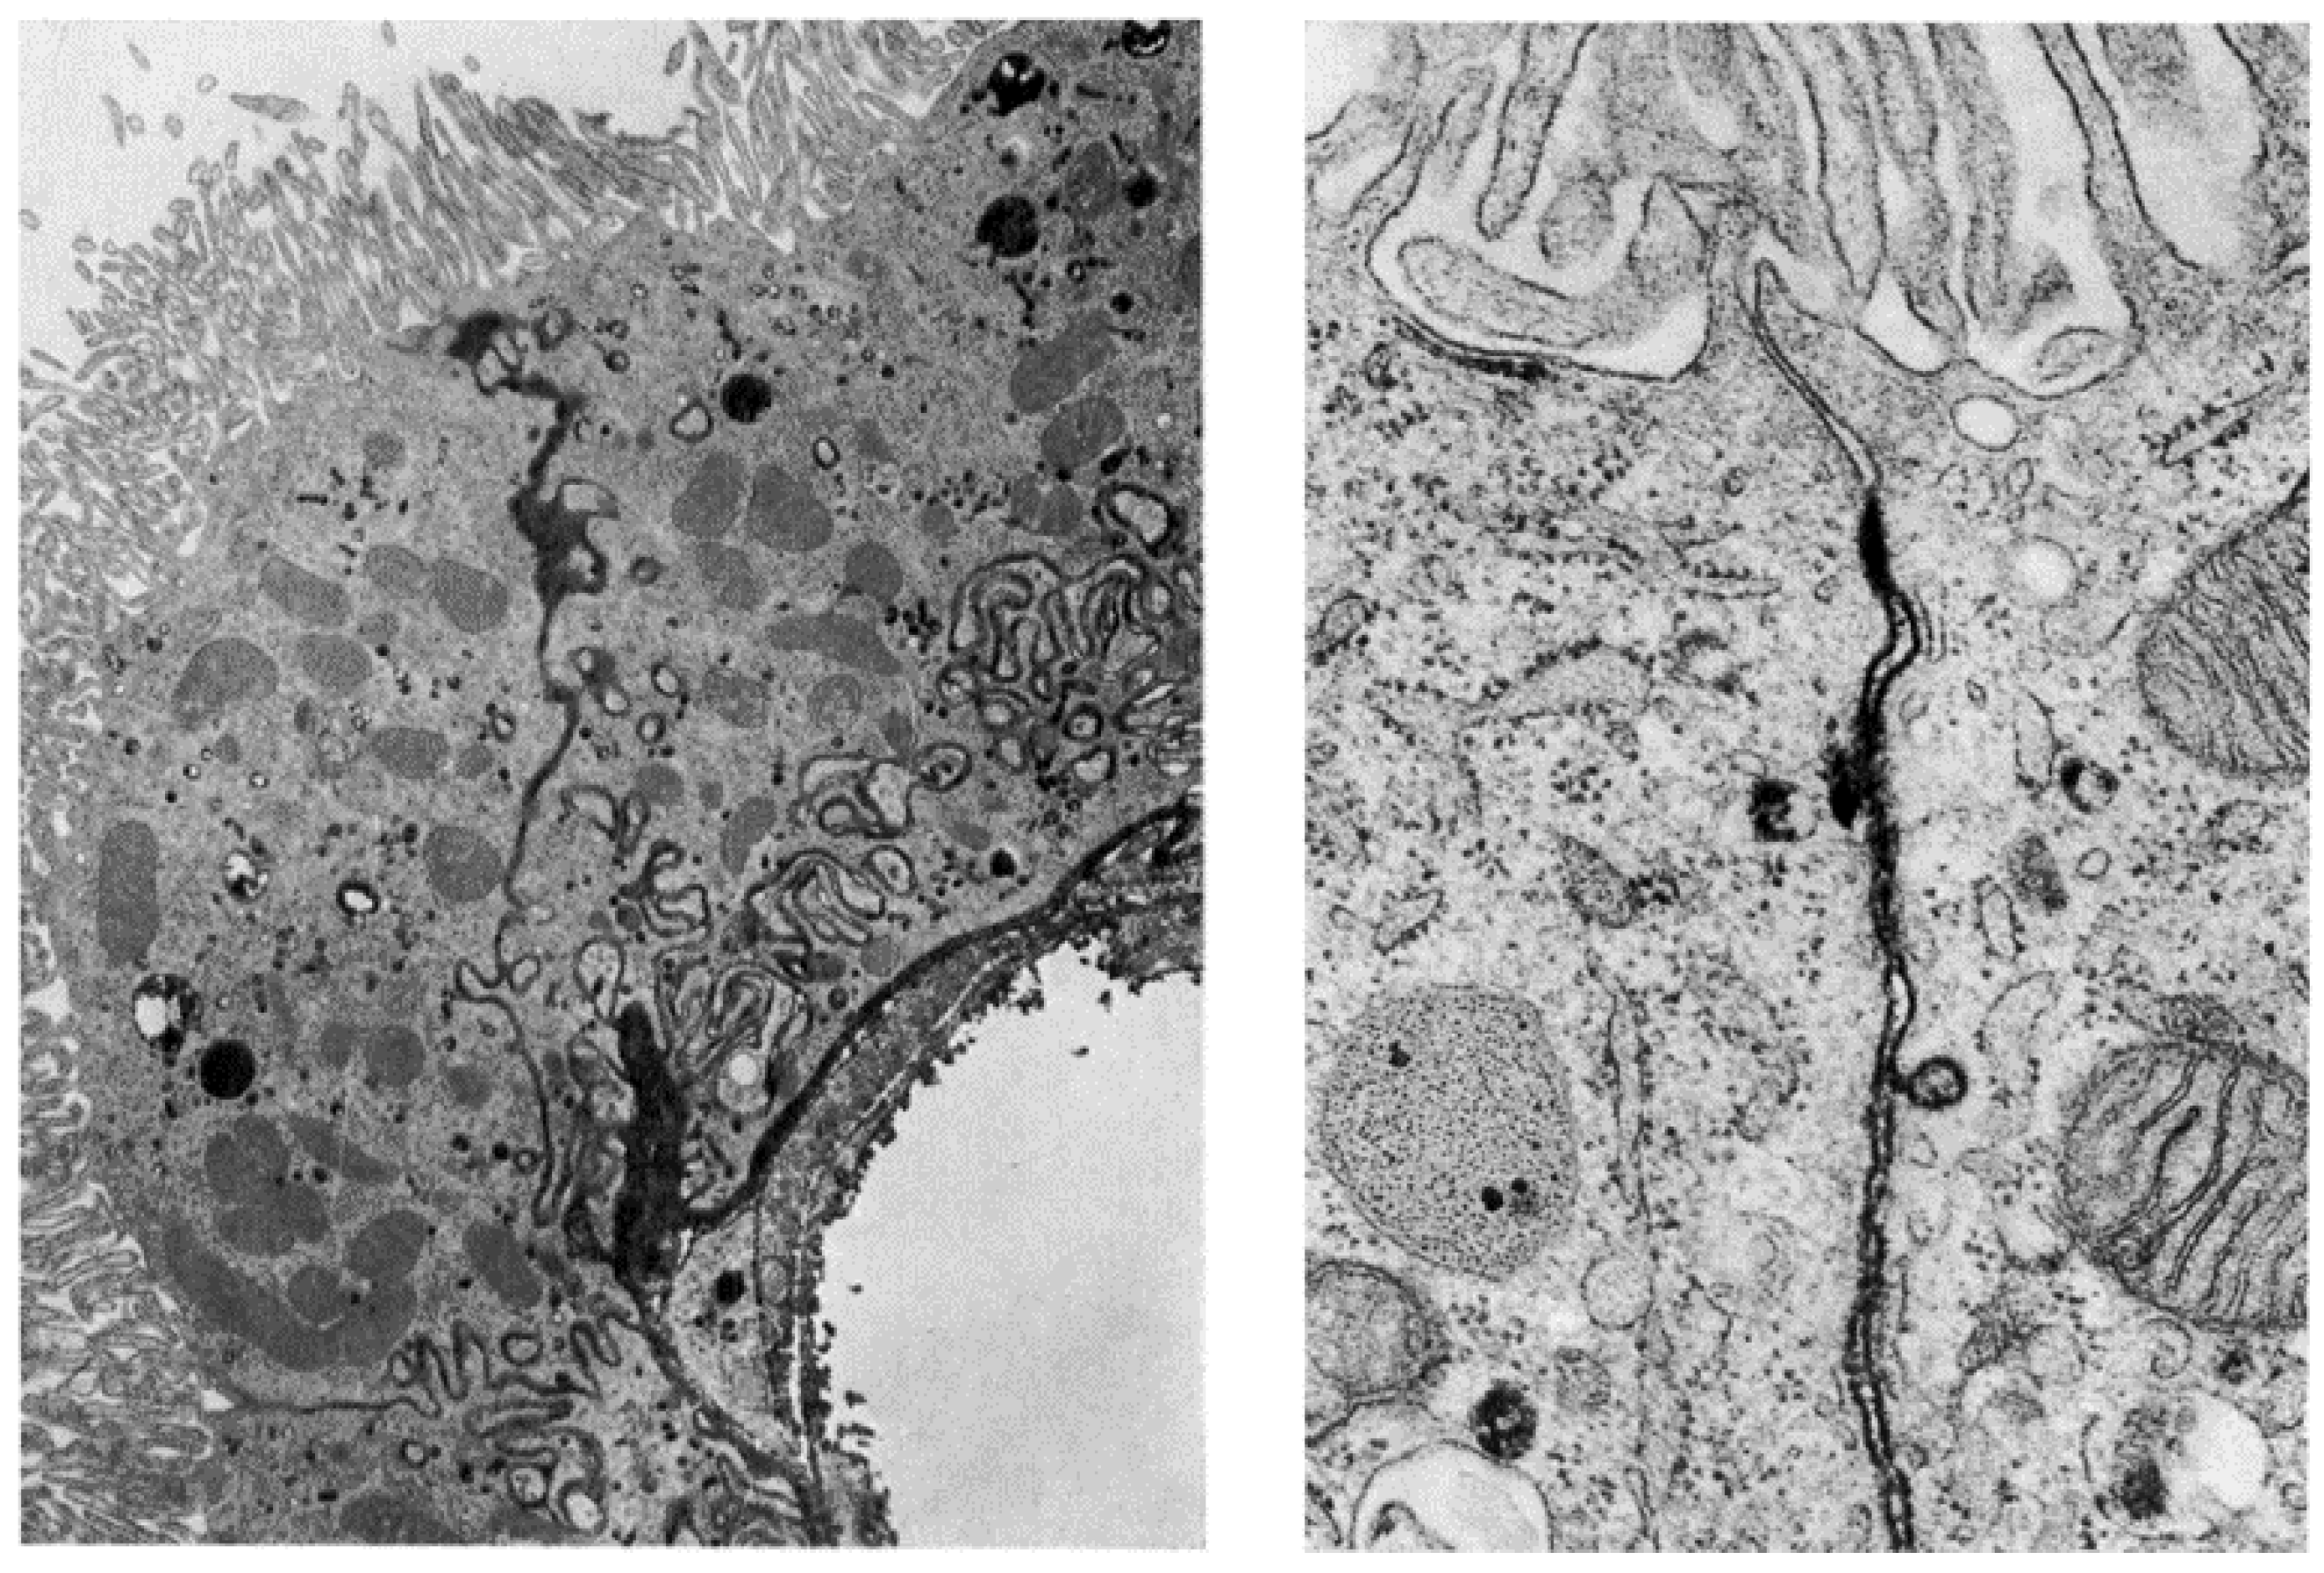

6.2.2. The Ependymal Cells